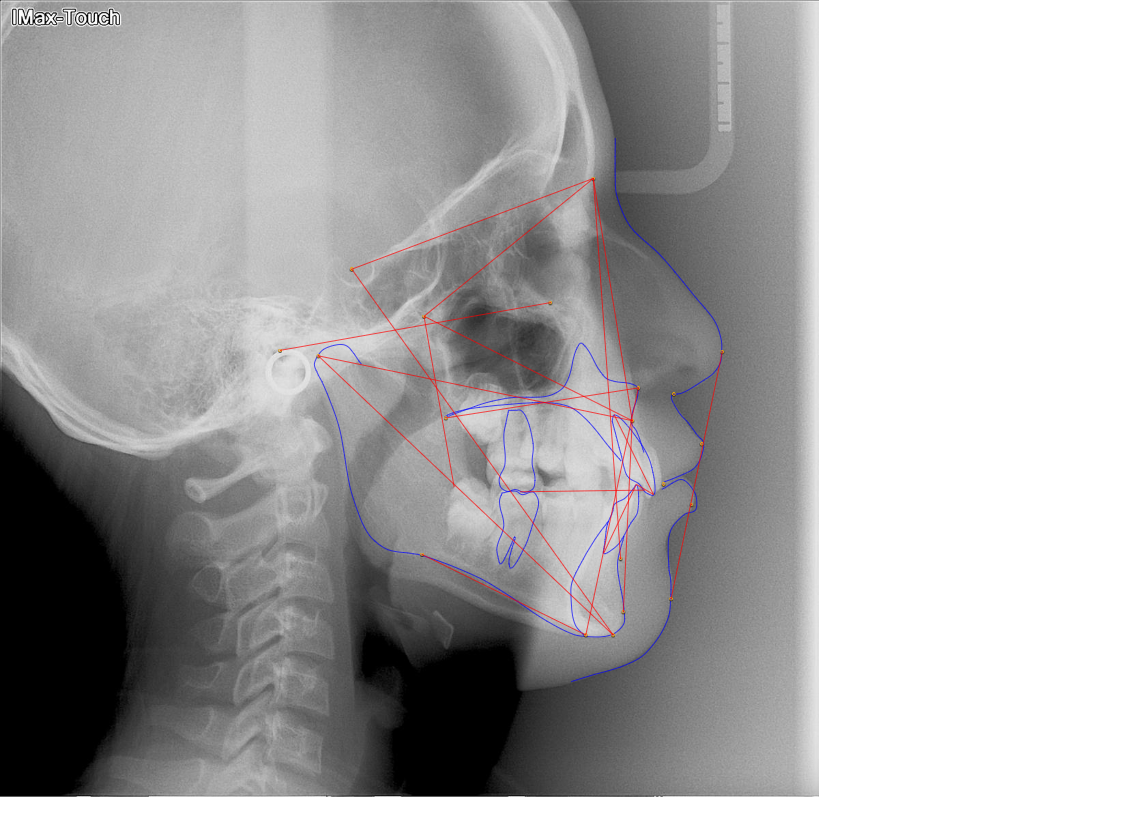

Many of us are not born with picture perfect teeth. For the straight teeth and alignment many people are searching for, braces is a common and effective treatment. Precision Dental Care uses the latest X-Ray technology to trace and model your teeth for your unique dental needs. From crooked teeth to alignment issues, braces can solve a variety of oral concerns.